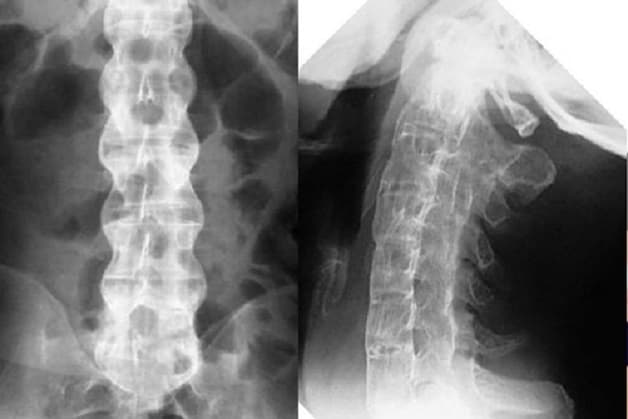

3.3. Chẩn đoán viêm dính khớp cột sống qua hình ảnh

Hình ảnh siêu âm, chụp chiếu đóng vai trò quan trọng trong việc chẩn đoán bệnh. X-quang cột sống có thể cho thấy sự viêm, tổn thương và biến dạng của các khớp cột sống. Tuy nhiên, phương pháp này khó có thể phát hiện bệnh ở giai đoạn sớm.

X-quang cột sống có thể cho thấy sự viêm, tổn thương và biến dạng của các khớp cột sống